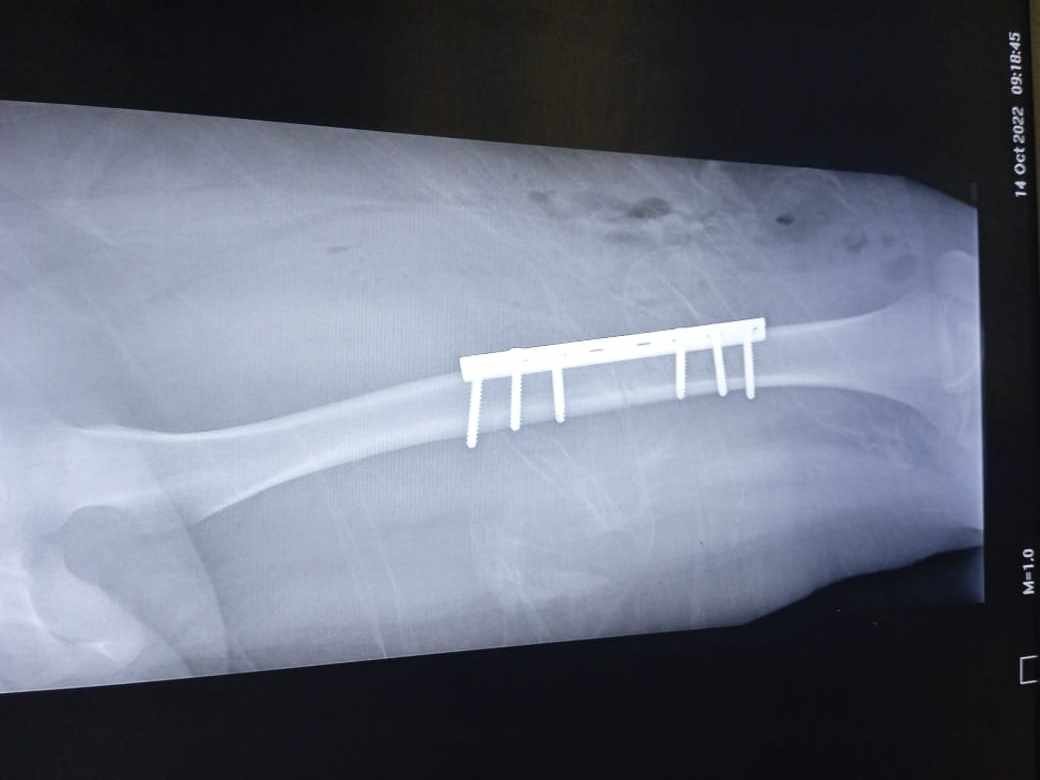

Fuentes oficiales confirmaron que debido a lo aparatoso del percance, la niña presentó fractura de fémur, por lo que fue necesario colocarle una placa y seis tornillos en la pierna izquierda.

La mamá de Arianna, Viridiana explicó que desde el arribo de la niña, recibió atención inmediata hasta completar el protocolo de estudios para la cirugía, donde le colocaron una placa de seis tornillos.